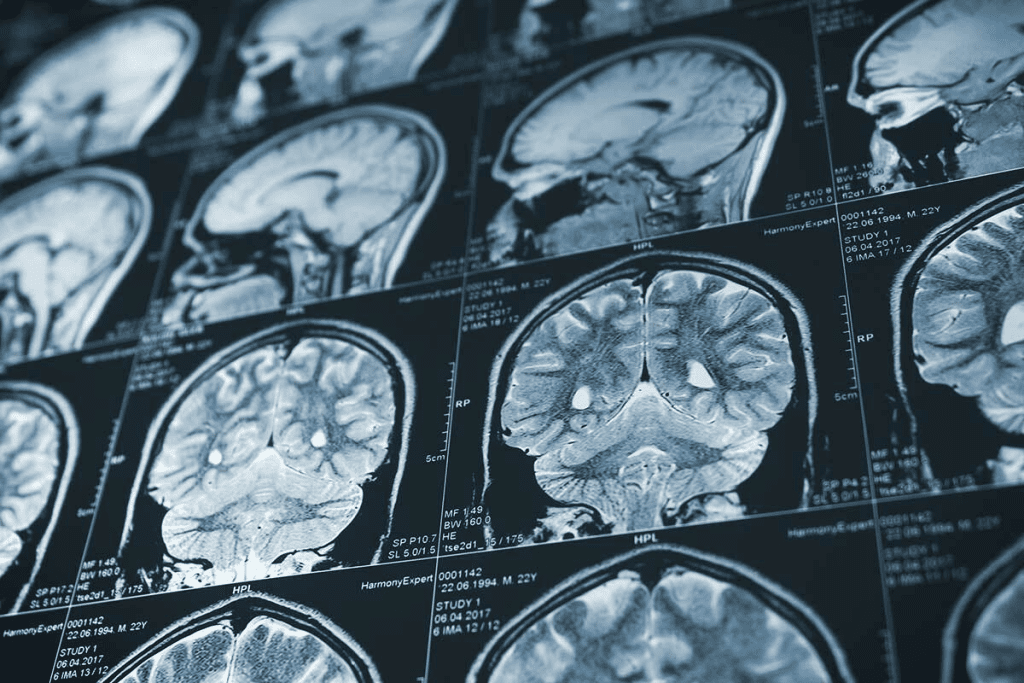

CT scans are key in finding cancer by showing the body’s inside parts clearly. They use X-rays from different angles to create detailed images. This helps doctors see inside the body.

CT scans use an X-ray source and detectors that move around the body. The X-rays pass through, showing how different tissues absorb them. A computer then makes images from this data.